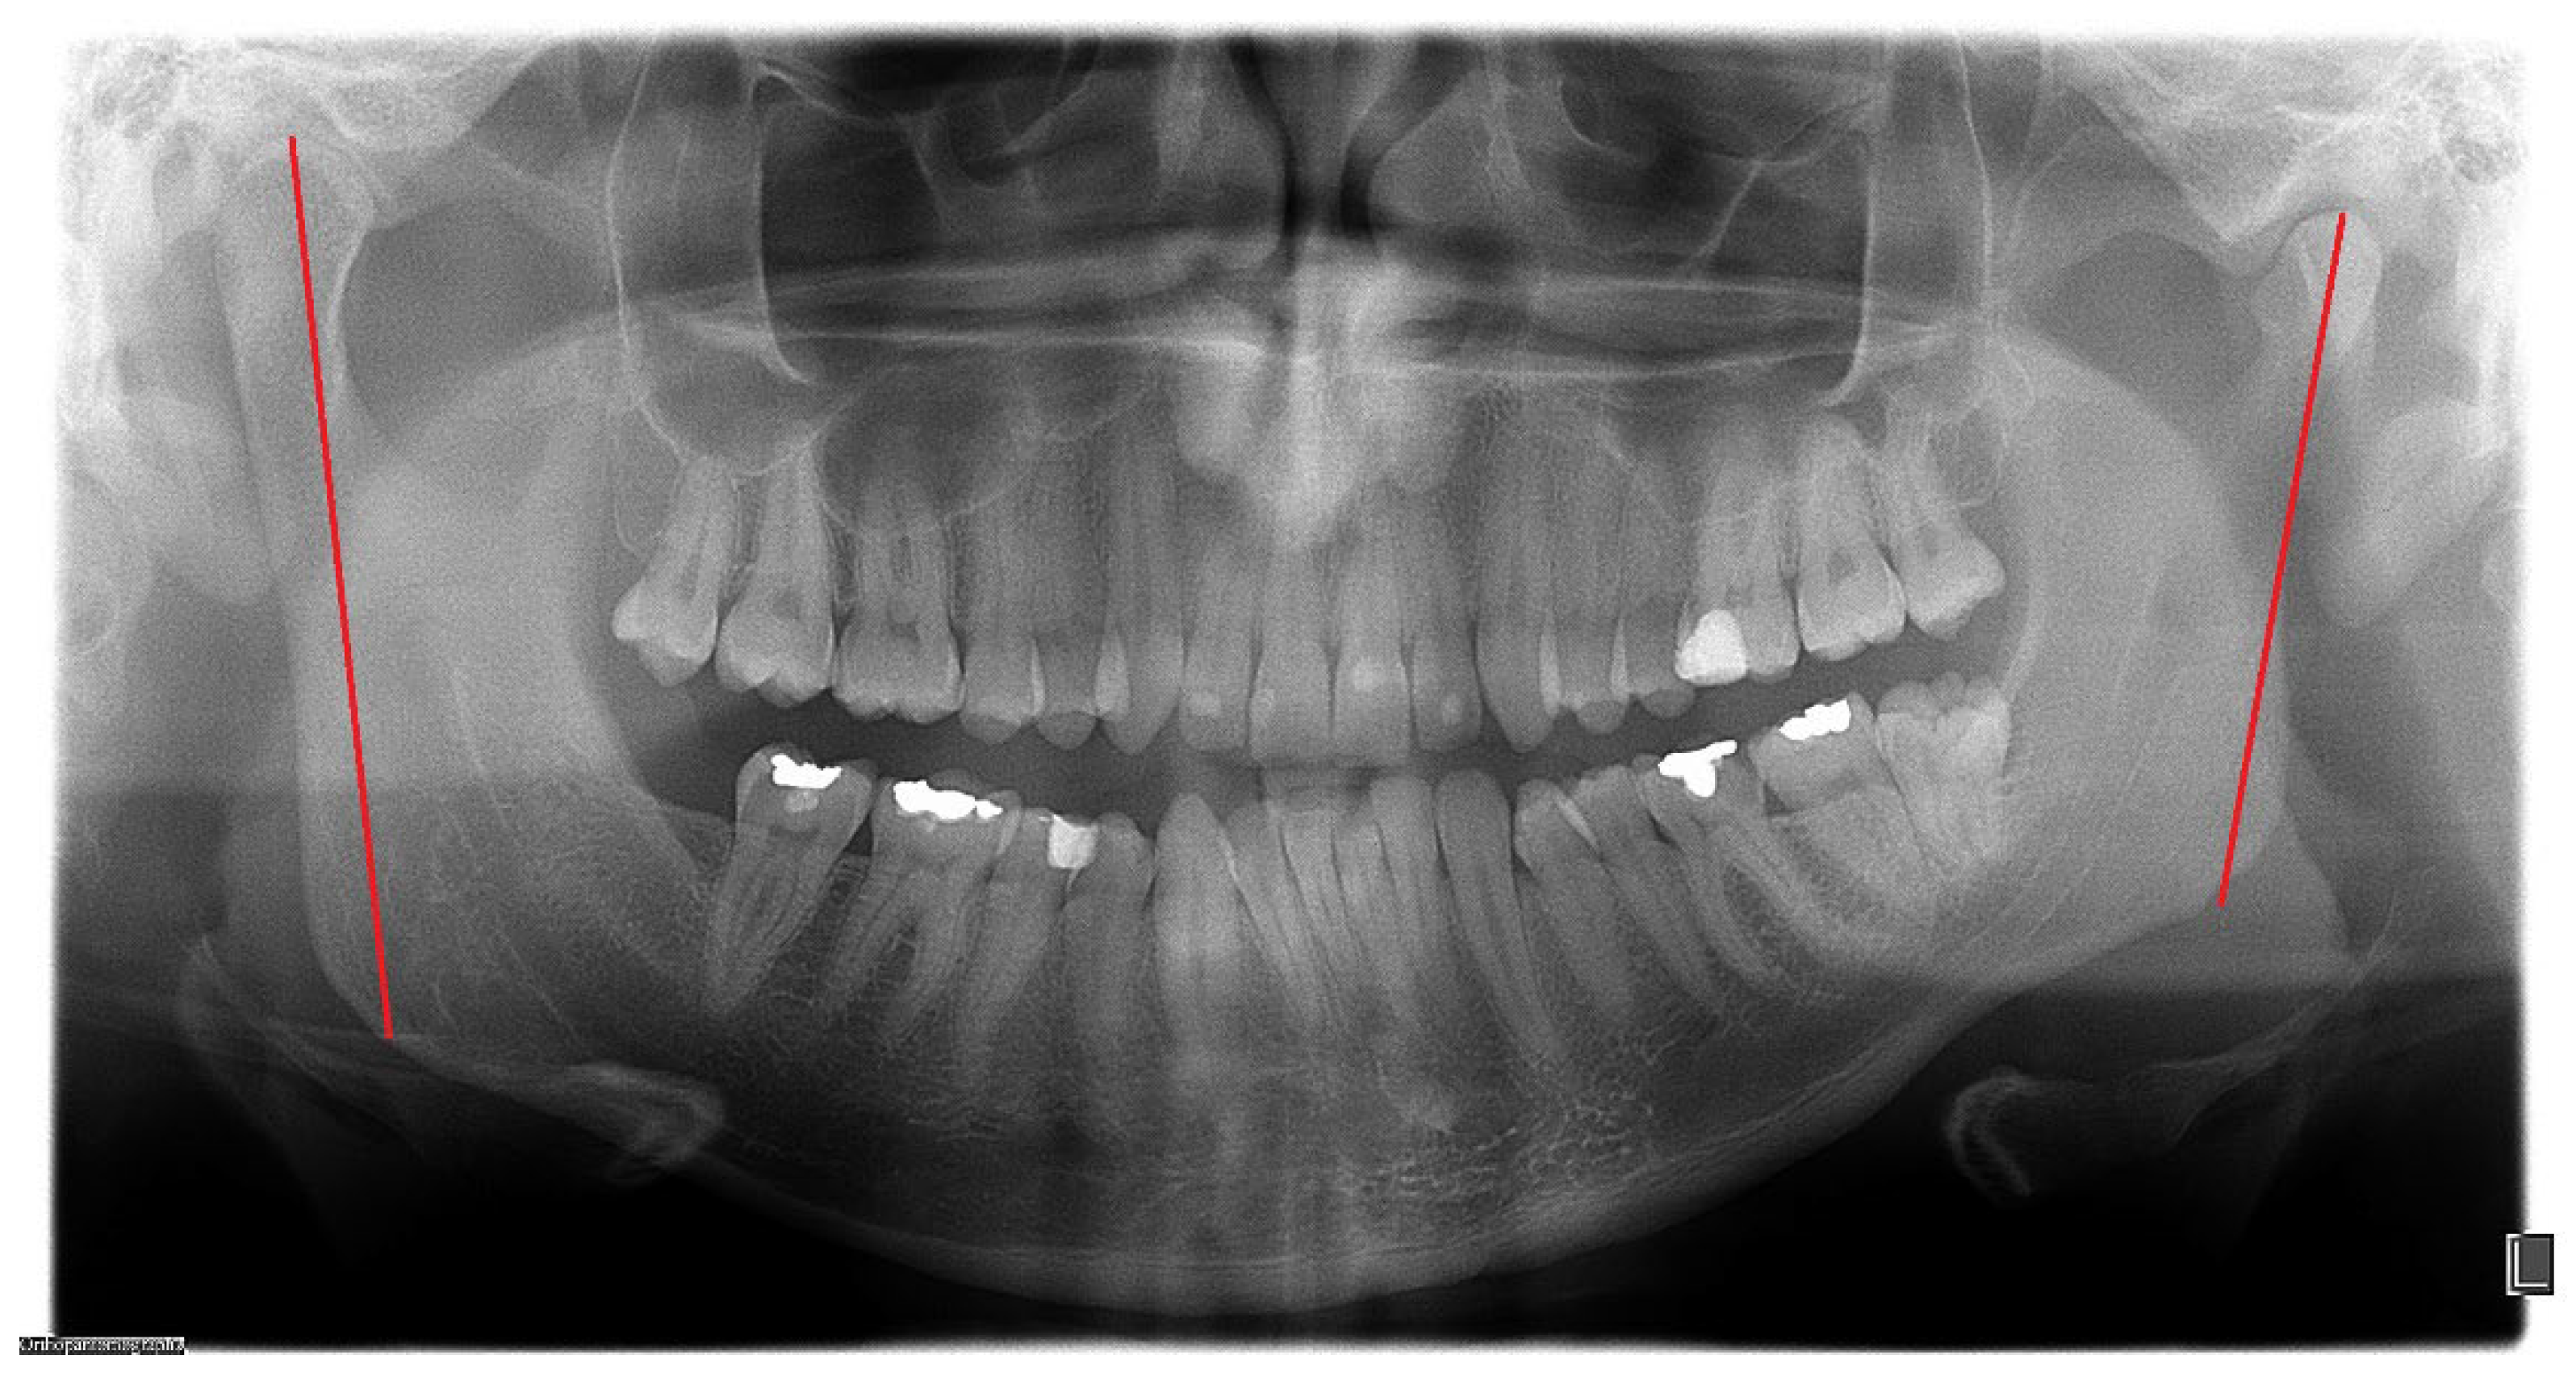

O—opposite side chin with normal position, chin shift towards the healthy side (Figure 4), chin area shifted towards the healthy side or asymmetrically overgrown on affected side;

Figure 4. Chin shifts towards the opposite side (degree of deviation marked with red line).